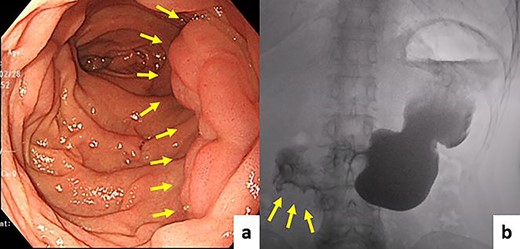

A 63-year-old woman was found to have a 7 × 8 mm, 0–IIc type tumor on the opposite side of the duodenal papilla in the follow-up EGD after endoscopic submucosal dissection for early gastric cancer (Fig. 3a). The pathological diagnosis was well-differentiated adenocarcinoma (Fig. 3b). CT revealed no lymph node metastasis or distant metastasis (Fig. 3c). We diagnosed early duodenal cancer as cT1aN0M0 (TNM classification). We planned to perform partial duodenectomy first and then pancreatoduodenectomy secondarily if the pathological examination of the resected specimen showed advanced duodenal cancer. After the duodenectomy, pedicled jejunal flap reconstruction was performed in the same manner as in Case 1. The pathological diagnosis was early duodenal cancer (pTisN0M0Stage0). The patient was discharged on the ninth postoperative day without any surgical complications. No tumor recurrence or gastrointestinal symptoms were reported 14 months after surgery. Follow-up EGD and upper gastrointestinal radiography did not show any signs of stenosis or motility disorder (Fig. 4a and b).

Follow-up EGD and upper gastrointestinal radiography did not show stenosis, diverticulum, or motility disorder. (a) EGD, (b) upper gastrointestinal radiography.